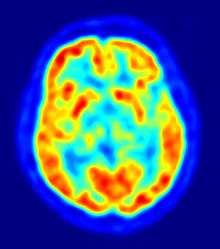

Sagittal PET scan at the level of the striatum. Hottest areas are the cortical grey matter and the striatum.

Fludeoxyglucose (18F) (FDG) PET scan of a healthy brain. Hotter areas reflect higher glucose uptake. A decreased activity in the basal ganglia can aid in diagnosing Parkinson's disease.

Computed tomography (CT) and conventional magnetic resonance imaging (MRI) brain scans of people with PD usually appear normal.[62] These techniques are nevertheless useful to rule out other diseases that can be secondary causes of parkinsonism, such as basal ganglia tumors, vascular pathology and hydrocephalus.[62] A specific technique of MRI, diffusion MRI, has been reported to be useful at discriminating between typical and atypical parkinsonism, although its exact diagnostic value is still under investigation.[62] Dopaminergic function in the basal ganglia can be measured with different PET and SPECT radioactive tracers. Examples are ioflupane (123I) (trade name DaTSCAN) and iometopane (Dopascan) for SPECT or fluorodeoxyglucose (18F)[62] and DTBZ[63] for PET. A pattern of reduced dopaminergic activity in the basal ganglia can aid in diagnosing PD.[62]